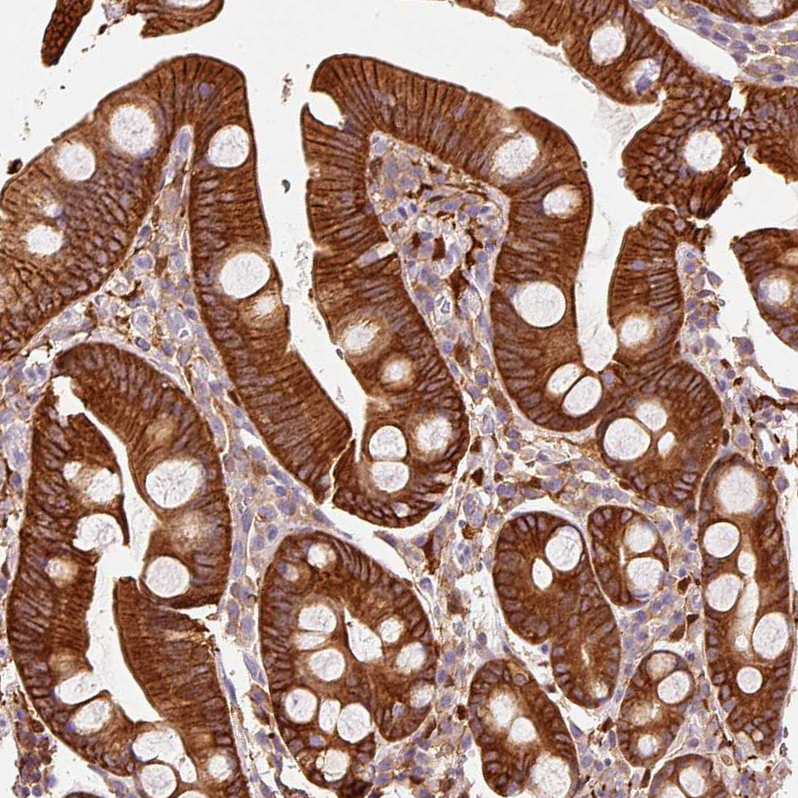

Immunohistochemical staining of human prostate cancer shows strong membranous and cytoplasmic positivity in tumor cells.